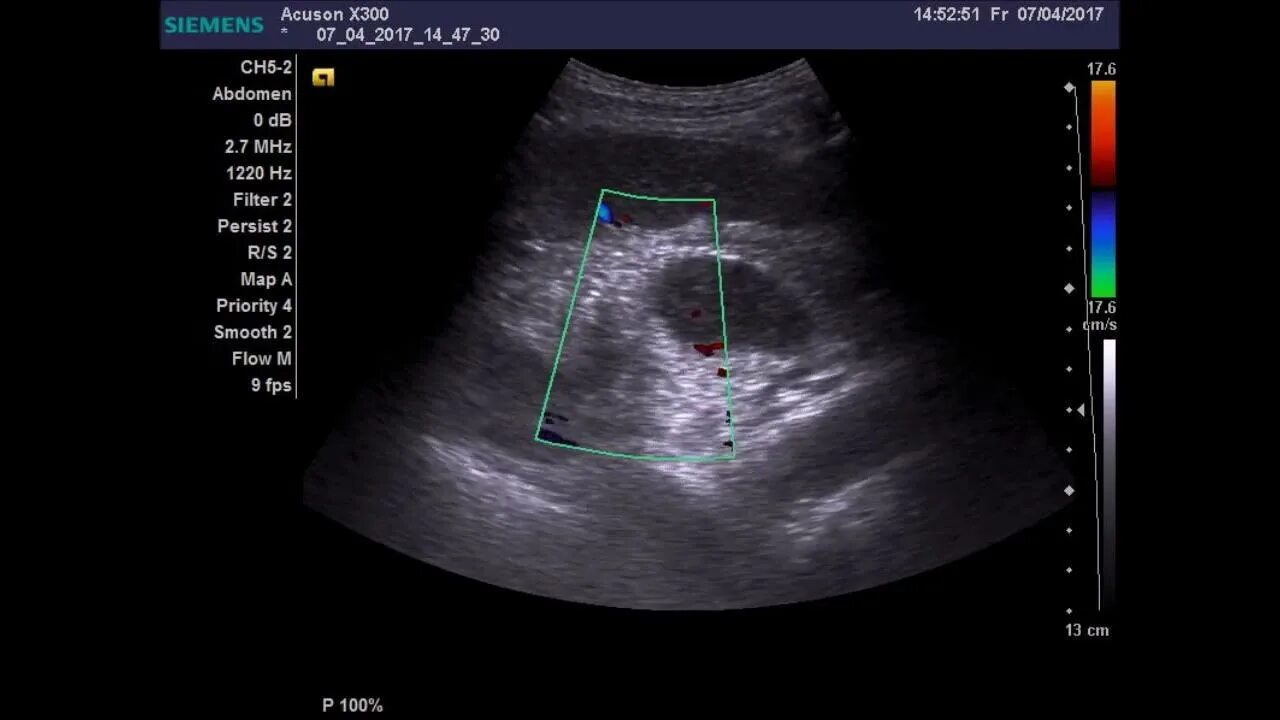

Подготовка к узи почек и забрюшинного пространства